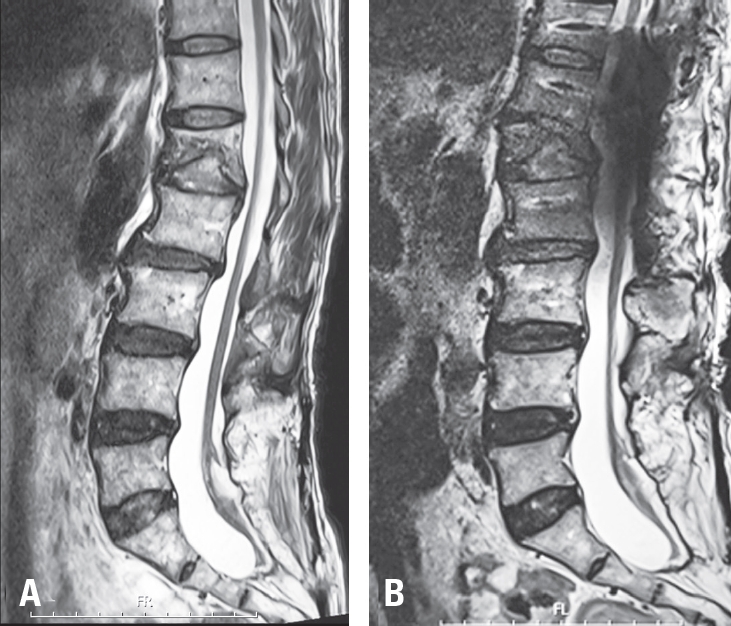

Fig. 4.

Pre-and post-operative sagittal T2WI MR image. (A) The marked kyphosis between T12 and L2 results in visible stretching of the spinal cord. (B) After reduction of the T12–L2 kyphosis and lowering of the spinal column height, the spinal cord appears slightly loosened and less tensioned.

Fig. 4. Pre-and post-operative sagittal T2WI MR image. (A) The marked kyphosis between T12 and L2 results in visible stretching of the spinal cord. (B) After reduction of the T12–L2 kyphosis and lowering of the spinal column height, the spinal cord appears slightly loosened and less tensioned.

The patient tolerated the procedure well without any intraoperative adverse events or signal changes in IONM. Immediate postoperative plain radiographs demonstrated a reduction in local kyphosis by approximately 28 degrees and a decrease in the spinal column height of approximately 10 mm at the osteotomy site (Fig. 2). MRI obtained on postoperative day 2 revealed distinct interval relaxation of the spinal cord compared with preoperative images, indicating an effective release of longitudinal tension (Fig. 4).